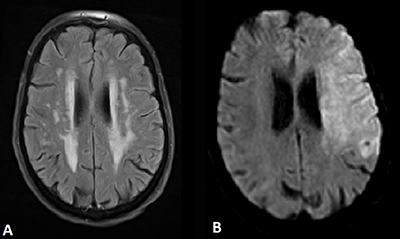

A 90-year-old female patient was brought to our hospital by ambulance after her husband found her somnolent and mute upon waking. Upon arrival, neurological and physical examinations showed spastic flexion of the right arm and deviation of gaze to the left. A so-called ‘wake-up stroke procedure’ was triggered and brain magnetic resonance imaging (MRI), including fluid-attenuation inversion-recovery (FLAIR) and diffusion weighted imaging (DWI) acquisitions, was immediately performed (Figure 1). Axial FLAIR images showed only leukoaraiosis (Figure 1A). DWI demonstrated high signal intensity in the territory of left middle cerebral artery (MCA) at high b-value (Figure 1B) with decreased apparent diffusion coefficient values. MR-angiography was precluded by patient’s movements.

Figure 1

MRI of the brain with (A) axial FLAIR image showing leukoaraiosis and (B) axial DWI showing high signal intensity in the territory of left MCA.